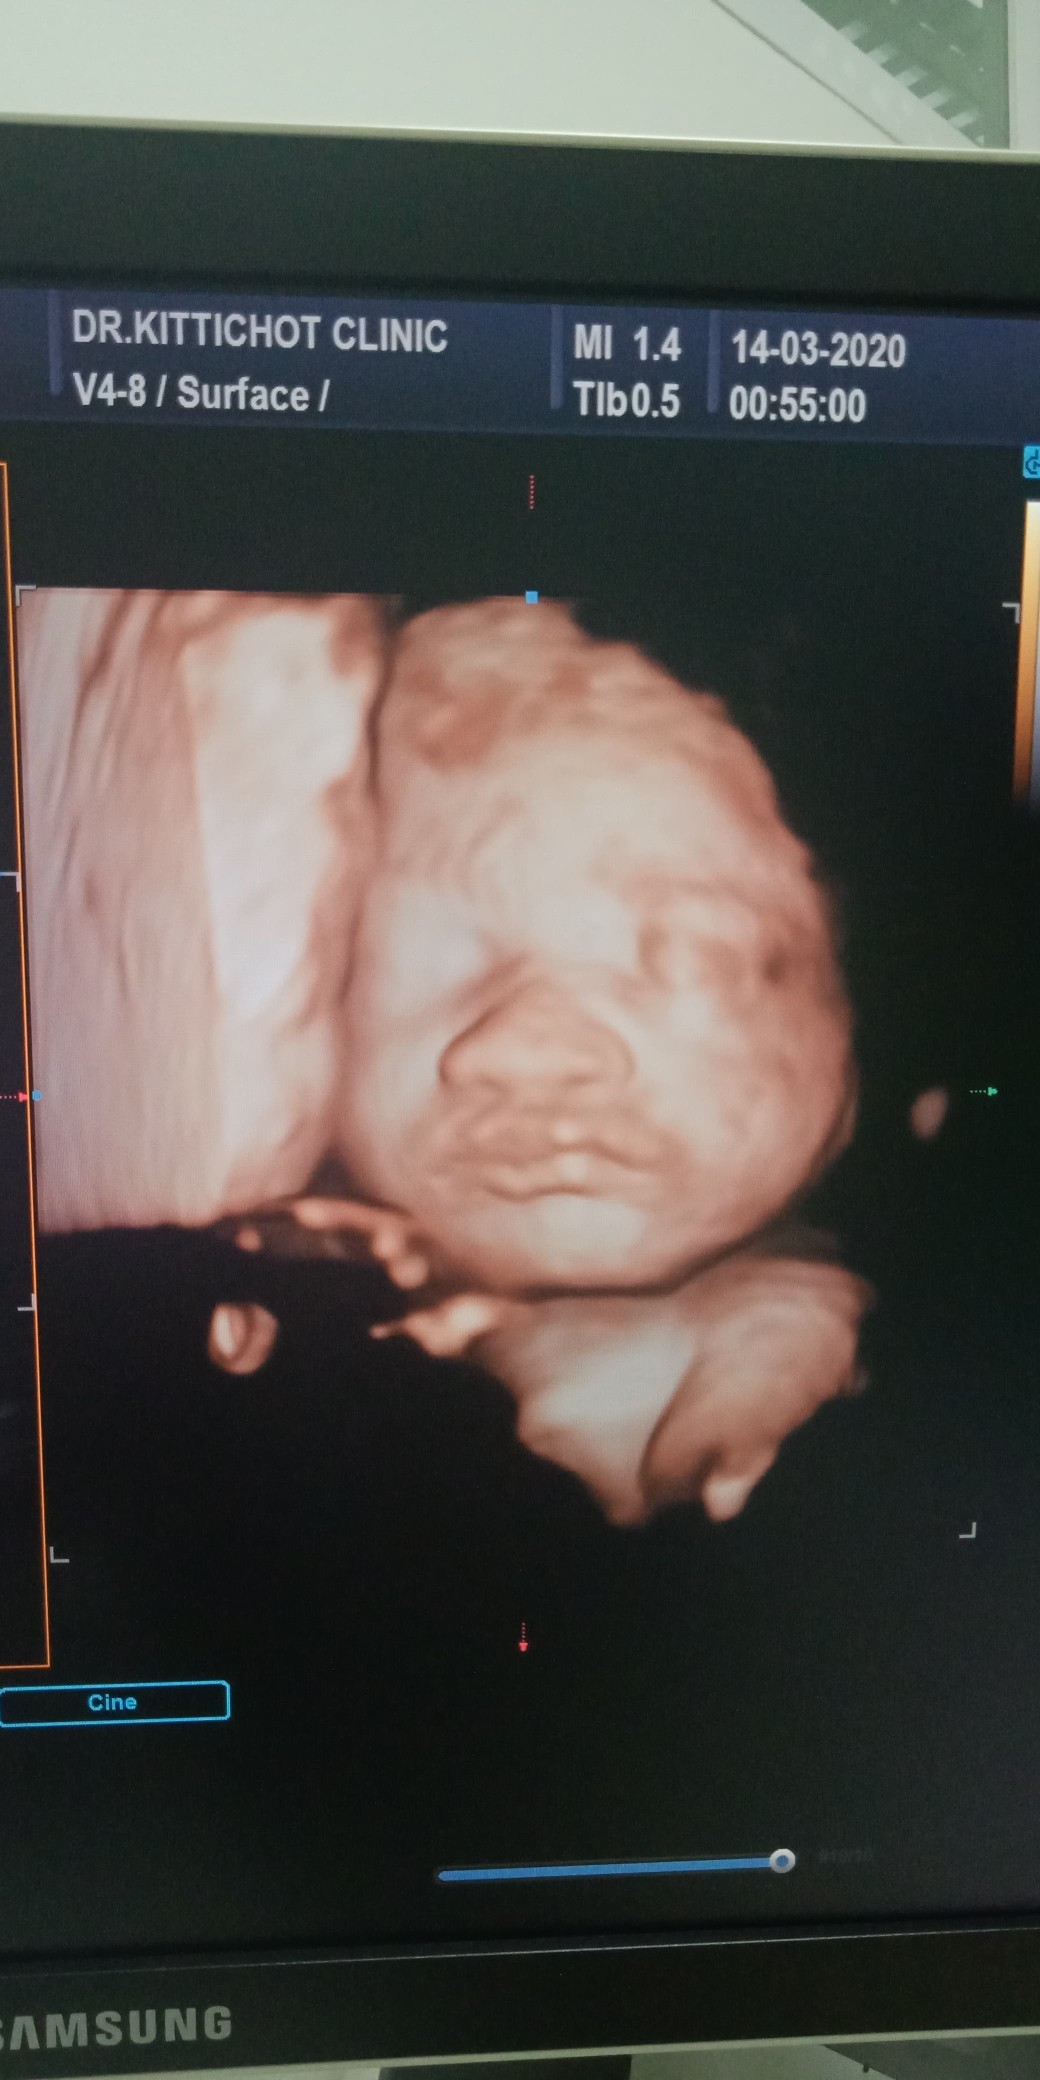

27wค่ะ